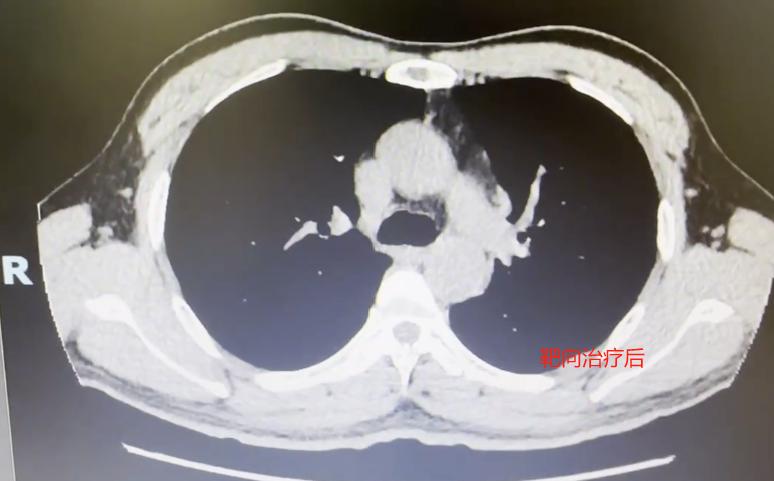

这位患者52岁,抽烟多年,前段时间突然嗓子哑了,一开始还以为是普通感冒引起的,自己吃了点消炎药,没想到不但没好,反而越来越严重...... 他去医院挂了耳鼻喉科,医生检查之后,却建议他再做个胸部CT,这一查,竟查出了中央型肺癌。 好端端的声音嘶哑,怎么会是肺癌?这其实是因为肿瘤长在肺部中央位置,侵犯到了喉返神经,这条神经正好控制着我们的声带活动,一旦受压,声音就会变哑。 所以,当喉镜检查找不到声音嘶哑的原因时,医生通常会建议再查一下胸部CT,排除肺部问题。 不幸中的万幸是,患者后续做了基因检测,发现存在ALK突变,可以用上针对性的靶向药。服药一个月后,复查显示肿瘤明显缩小,连说话声音也清亮了不少。 通过这个病例,也想给大家提个醒: 如果您有长期吸烟习惯、常接触二手烟,或者家里有肺癌家族史,记得定期做早期癌症筛查,别等有症状了再查; 这类高危人群,如果突然出现声音嘶哑,又没有感冒或喉咙痛这类情况,建议先去耳鼻喉科做个喉镜。如果喉镜没问题,就要考虑是不是肺部原因,必要时做个胸部CT。[玫瑰][作揖]MCN双量进阶计划胸外科乔贵宾医生 [心]附:线下免费义诊!11月21日(周五上午),在南方医科大学珠江医院 门诊大厅, 义诊与健康宣教活动来了,欢迎朋友们来参加~